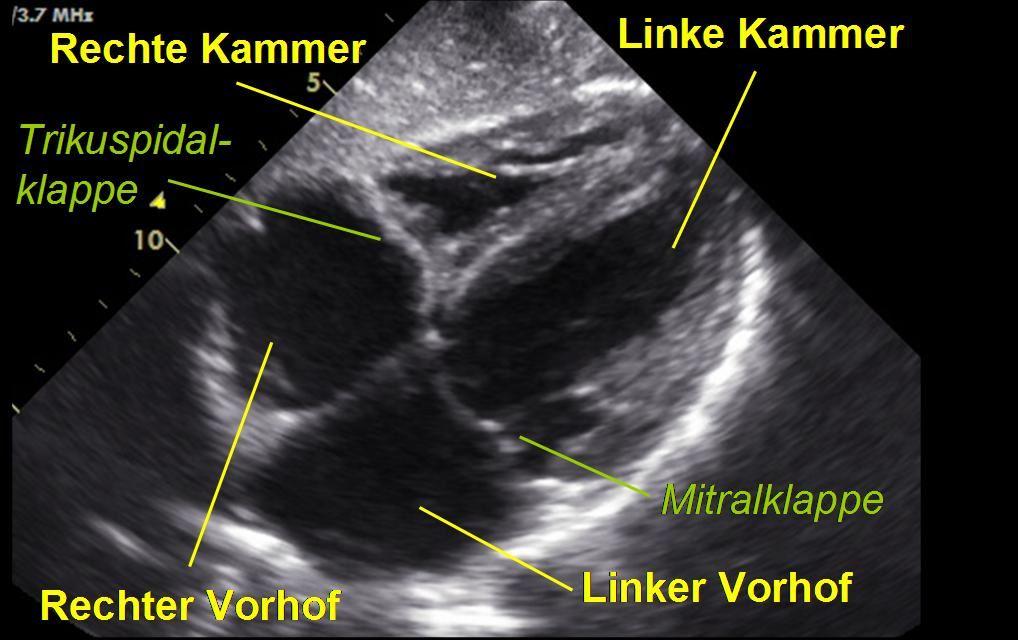

Die Echokardiographie ist die wichtigste bildgebende Untersuchung der Kardiologie. Sie erlaubt uns eine schnelle und für den Patienten harmlose Abbildung des Herzens und der angeschlossenen Gefäße mittels Ultraschall. Der rasante technologische Fortschritt der letzten Jahre hat zur Entwicklung modernster Geräte geführt, die durch den geübten Untersucher eine exakte Darstellung von Anatomie und Funktion ermöglicht. Der Farbdoppler bietet zusätzliche Informationen, indem er den Blutfluss im Herzen visualisiert.

Eine Standard-Untersuchung kann folgende Informationen bieten:

- Größe der Herzhöhlen

- Wanddicke der Herzmuskulatur

- Pumpleistung der linken und rechten Herzkammer

- Störungen der Kontraktilität der Herzmuskulatur

- Dehnungsfunktion des Herzens

- Größe der Hauptschlagader

- Funktion der vier Herzklappen

- Anatomische Besonderheiten

- Auffälligkeiten des Herzbeutels